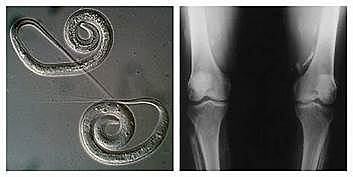

• Programa de Lucha contra la Oncocercosis

Programa de Lucha contra la Oncocercosis

En colaboración con el Banco Mundial, el Programa de las Naciones Unidas para el Desarrollo, y la Organización de las Naciones Unidas para la Agricultura y la Alimentación.

• Programa Especial de Investigaciones y Enseñanzas sobre Enfermedades Tropicales

Programa Especial de Investigaciones y Enseñanzas sobre Enfermedades Tropicales

Coordinación de las actividades mundiales contra enfermedades infecciosas que afectan a poblaciones pobres y marginadas, así como para prestarles apoyo e influir en ellas.